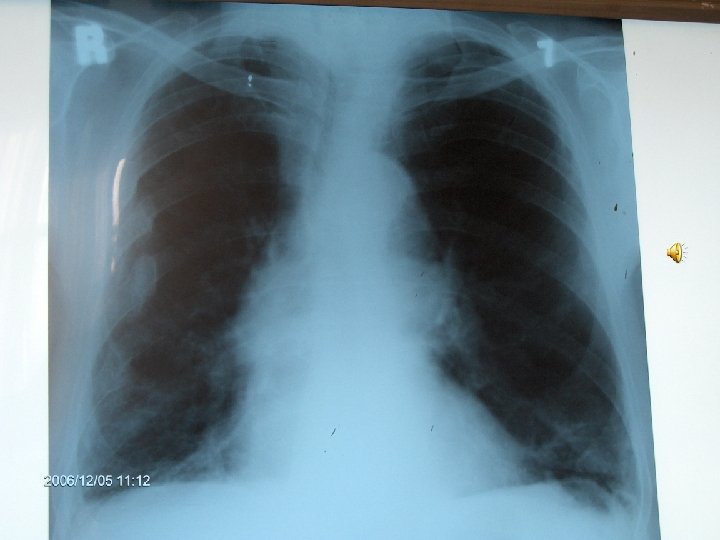

MS 76 yaşında, erkek hasta İş adamı

YAKINMASI Nefes darlığı (eforla) l Öksürük l Balgam çıkarma (mukoit) l Halsizlik l

Özgeçmiş l Kot kırıkları 4 yıl önce, travma öyküsü yok

ALIŞKANLIKLARI 50 paket/yıl sigara 10 yıldır bırakmış

FİZİK MUAYENE l l l Genel durum iyi, bilinç açık Dispne (+) Ateş: 36. 8 ‘C TA: 150/90 mm. Hg Nabız 100/dk, ritmik Kalp sesleri: S 1, S 2 doğal. S 3(-)

Solunum Sistemi l DSS: 30/dk, l l l torakoabdominal. Bilateral solunum sesleri azalmış. Ekspiryum uzun Tek tük wheezing mevcut

Fizik Muayene Dispneik Ödem Karaciğer kot kenarını geçiyor

SFT FVC: 1740 ml(%59) FEV 1: 640 ml(%29) FEV 1/FVC: %37 FEF 25 -75: 0, 22(%9)

VOLÜMLER Pletismografik TLC: 7240 ml(%136) RV: 3780 ml(%140) RV/TLC: %52

DİFÜZYON KAPASİTESİ DLCO m. L/mm. Hg/dak l DLCO/VA m. L/mm. Hg/dak /L l %26 %32

AKG Pa. O 2: 47. 2 mm. Hg Pa. CO 2: 39 mm. Hg Sa. O 2: %85 p. H: 7. 4 HCO 3: 28. 4